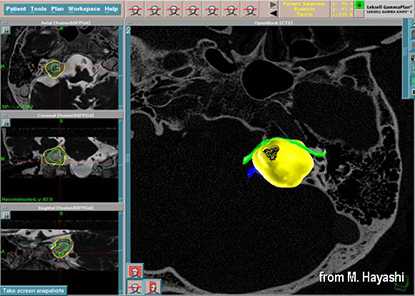

До начала радиохирургического лечения проводится обследование, позволяющее определить точное положение опухоли и прилегающих нервных образований. Выполняется трехмерная реконструкция, отображающая детальную микрохирургическую анатомию этой области. Для этой цели с помощью МРТ получают четкую визуализацию опухоли и нервов во внутреннем слуховом проходе и области мосто-мозжечкового угла.

С помощью планирующей системы Gamma Planи автоматической позиционирующей системывозможно проводить очень точное облучение опухоли (точность 0,5 мм), избегаяповреждения черепных нервов и других важных отделов мозга.

Клинический случай из практики отделения Радиохирургии онкологической клиники МИБС. Пациент Т., 1956 г.р. Тригеминальная невралгия справа и слева, на фоне рассеянного склероза. Медикаментозное лечение без клинического эффекта. Гамма-нож единственный возможный вариант лечения, оперативное лечение при такой форме заболевания не применяется. Радиохирургическое лечение Gamma-Knife с двух сторон с интервалом 10 месяцев. Уменьшение боли после радиохирургического лечения на аппарате Gamma-Knife через 3 и 5 месяцев.

Иллюстрация плана лечения на Гамма-ноже, проведенного в вышеупомянутом клиническом случае. Крохотная зона, находящаяся внутри зеленого контура, - и есть точка подведения высокой дозы радиохирургии, которая разрушает тройничный нерв, бесконтактно избавляя от мучительной боли. За один сеанс, проходящий без анестезии и разрезов.